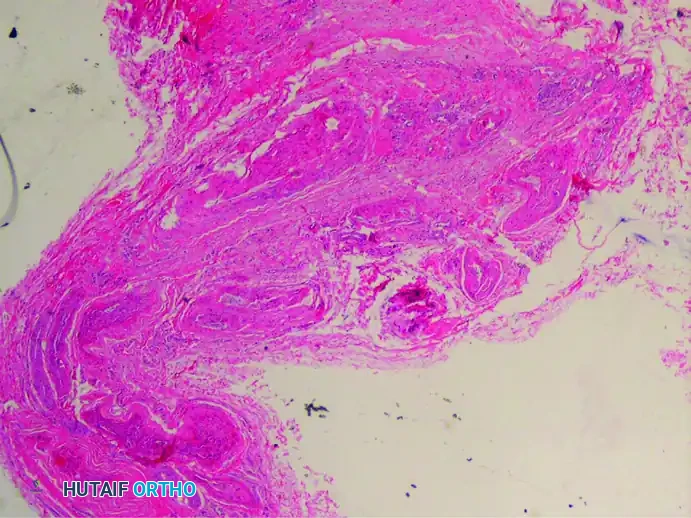

4. Associated Bursal Tissue

It is highly frequent to find reactive bursal tissue accompanying the excised nerve specimen. This intermetatarsal bursitis is often the initial source of inflammation that subsequently leads to the perineural fibrosis of the adjacent nerve.

(Hematoxylin and eosin stain showing an associated small bursa)